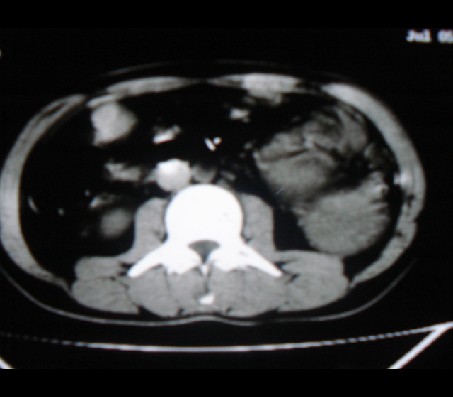

标题: CT20935:左肾占位,请会诊!

男性,35岁,ct号26189,左侧腰痛并血尿一天入院。

左肾癌侵犯肾盂可能性大,建议增强.

考虑左肾癌可能性大,建议增强扫描。

左肾癌侵犯肾盂可能性大。

肾癌侵犯肾盂,肾盂出血,肾盂内为血肿

首先考虑恶性肿瘤性病变,考虑左肾癌可能性大,建议增强扫描。